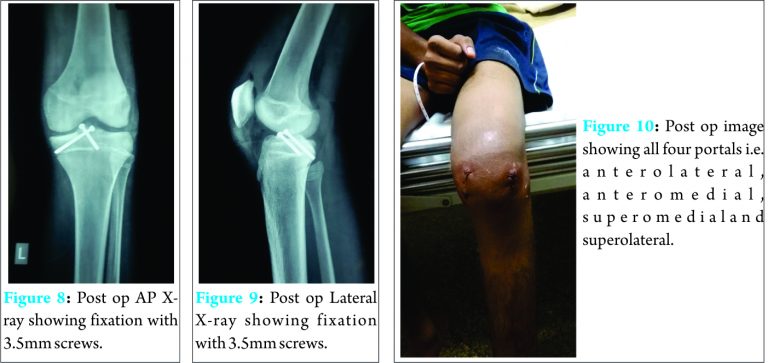

Fracture was reduced with the help of ACL zig and under C- Arm guidance, provisionally fixed with guide wire from superolateral portal taking care not to cross physis. As it was a large fragment, it did not sit completely from medial side so another wire was used from superomedial portal to fix medial side of fragment perpendicular to lateral wire, again without crossing the physis. Two 3.5 mm partially threaded cannulated screws (Zimmer) were directly used; 45mm from lateral side and 35mm from medial side [Fig. 7]. Stability of the fragment was assessed with a probe and was found to be very stable [Fig. 6]. Post-operatively, patient was given a knee brace [Fig. 10].Post-op X-rays showed proper position of both screws [Fig. 8, 9 ]. He was allowed to walk full weight bearing with the knee brace and with support. Knee ROM from 0-90 was allowed for 2 weeks then 0-120 for next 2 weeks. After one month, he was allowed to walk without knee brace. At 6 months, patients was allowed to run. Now we have 8 months follow-up.